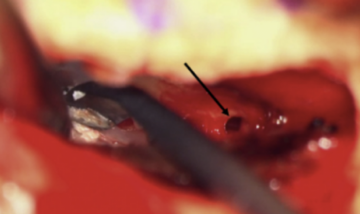

The transmastoid approach and the middle fossa craniotomy are the two main methods of surgical management where the surgeon resurfaces, plugs, or caps the bony dehiscence. Using the middle fossa craniotomy allows the surgeon to directly visualize the bony dehiscence and has been reported to effectively alleviate vestibular issues. Although the dehiscence cannot be visualized through the transmastoid approach, it offers a slightly lower risk of cerebrospinal fluid leak and intracranial complications. Dehiscences can be resurfaced only through the middle fossa craniotomy while plugging can use either approach. However, using the transmastoid approach to plug increases the risk of harming vestibular and cochlear structures, which results in a higher risk of hearing loss. Middle fossa craniotomy resurfacing also has a slightly higher risk of seizure than the transmastoid approach because the temporal lobe needs to be retracted. There are always risks associated with surgery, but most patients report a high level of improvement after surgical treatment.